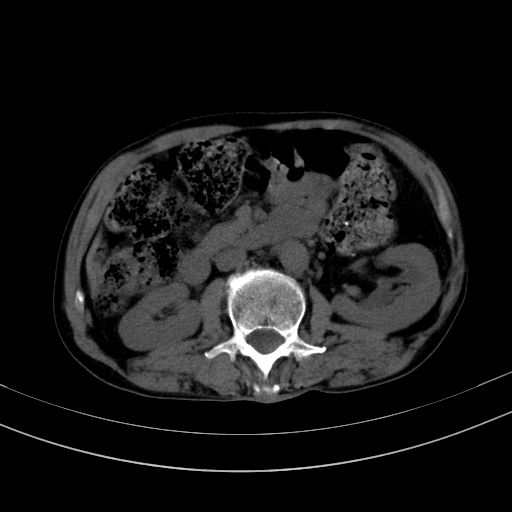

以下是引用37度在2010-1-9 14:37:00的发言:[br]1.双肾囊肿,左肾积水结石,.胆总管轻度扩张;[br]2.病灶在腹膜外,考虑纤维瘤。

以下是引用dyqct在2010-1-9 17:56:00的发言:[br]考虑:1.双肾囊肿,左肾积水结石、旋转不良。[br] 2.右侧腹直肌血肿或纤维瘤。[br]肠道准备不好。做个增强。